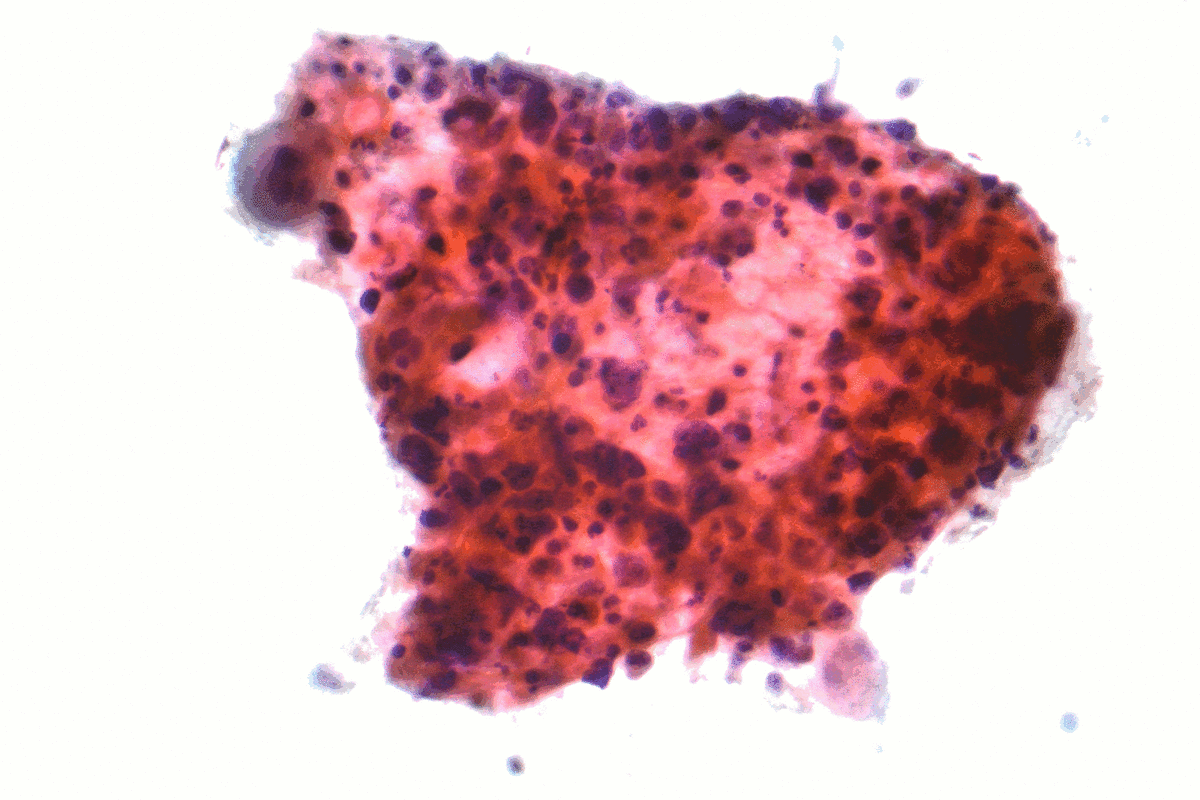

سرطان الخلايا الصغيرة ويكيبيديا

سرطان الخلايا الصغيرة المعرفة

سرطان الخلايا الصغيرة Wikiwand